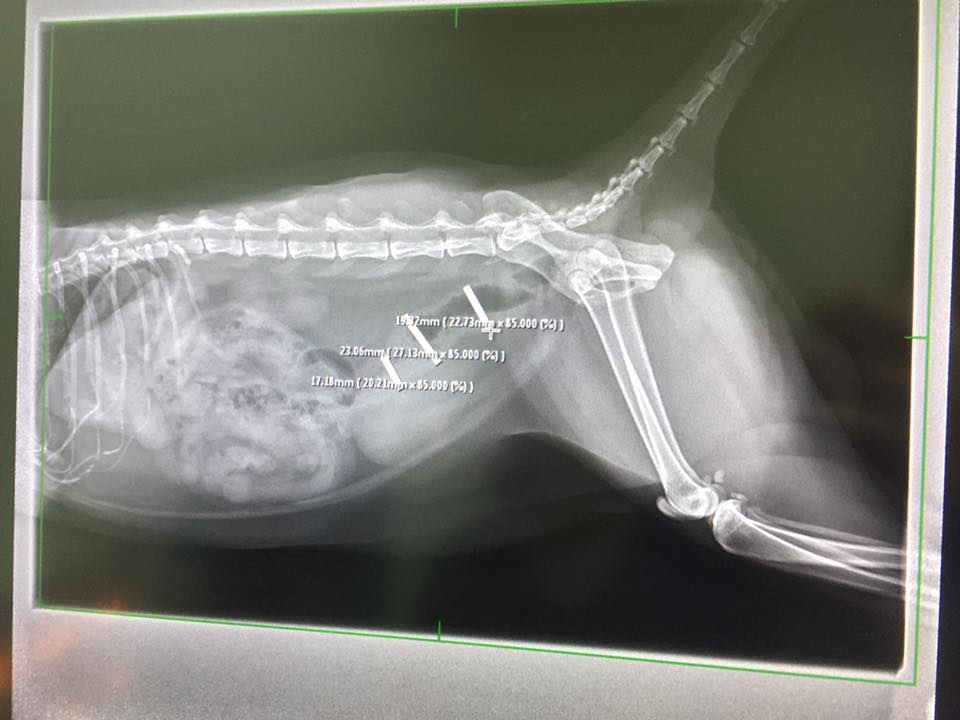

醫師說x光片上顯示小黃的腸子尾端有縮小的趨勢,這對小黃的狀況來講是好的。